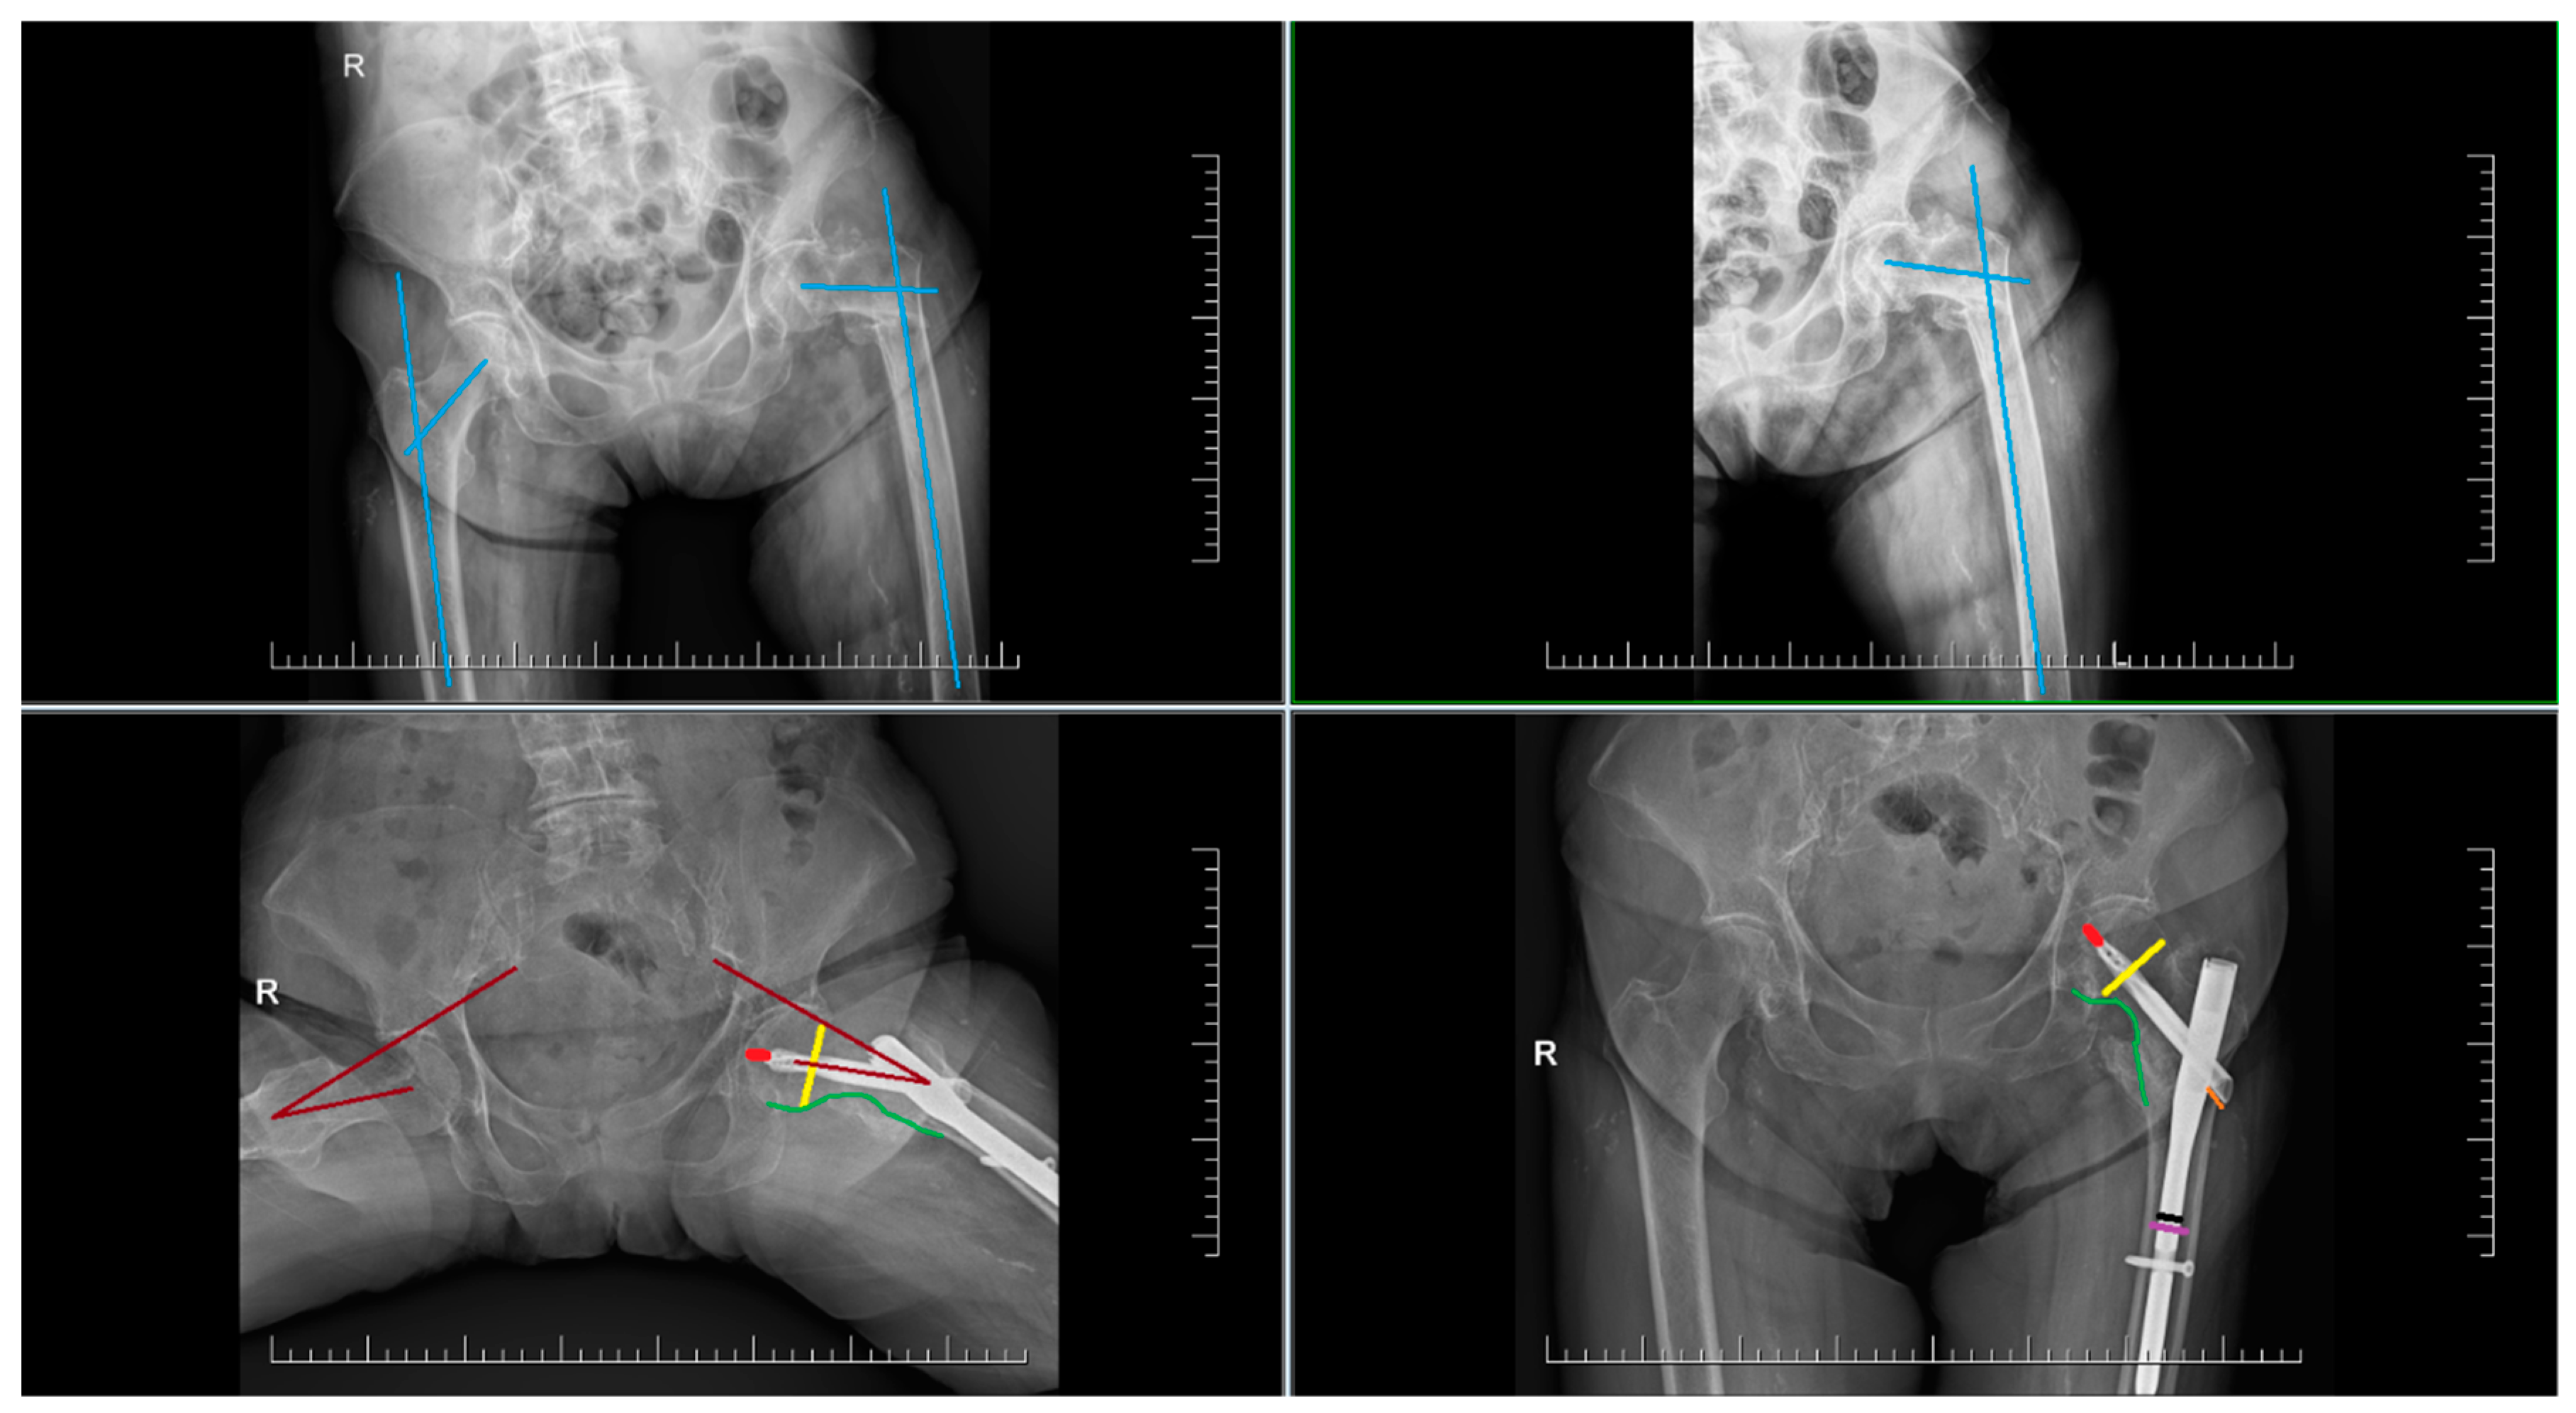

By evaluating the X-ray parameters, eight patients in the cohort in whom postoperative varus deformities of the femoral neck were greater than 10° were founded. Four patients did not have cement augmentation and four had cement augmentation of the nail. In three cases, the blade cut-out and, thus, failure of osteosynthesis was identified. In two women and one man with blade cut-out, a TFN-A implant without cement augmentation was implanted (Figure 3, Figure 4 and Figure 5). In these three cases, the medial cortical line and anterior cortical line were repositioned within 3 mm of dislocation at the anatomical interface. The blade cut-out in the group with cement augmentation was not observed.

Figure 5. Failure of osteosynthesis and cut-out of the blade after osteosynthesis using TFNA. Extraction of TFNA and implantation of a total hip endoprosthesis.

From clear X-ray images of the pelvis, the collum-diaphyseal (CCD) angle on the contralateral side before surgery was evaluated (Figure 1). From the same X-ray images, the type of fracture according to the AO/OTA classification was determined. After surgery, the following in AP projections were evaluated: CCD angle, fracture shortening, the distance between the tip of the blade and the subchondral bone, known as TAD (tip-apex distance) in two projections, the distance between the lateral end of the blade and the nail, and the position/course of the blade in the femoral head. TAD was calculated according to Baumgaertner’s description [9]. The position of the blade in the femoral head was determined based on the work of Cleveland [10]. The quality of reduction by evaluating the medial cortical line was assed, where we assessed both the disrupted continuity and displacement of fragments or the presence of a gap along this line. If the dislocation or gap was greater than 3 mm, the reduction in the area of the medial cortical line (Adam’s arc) was assessed as non-anatomical.

One of the complications of treatment is the lateral prominence of the blade (Figure 3). Statistical analysis showed that the average difference between the BN-BE (blade nail–blade end) distance immediately after surgery and after 6 months was 5.52 mm (p = ˂0.001).